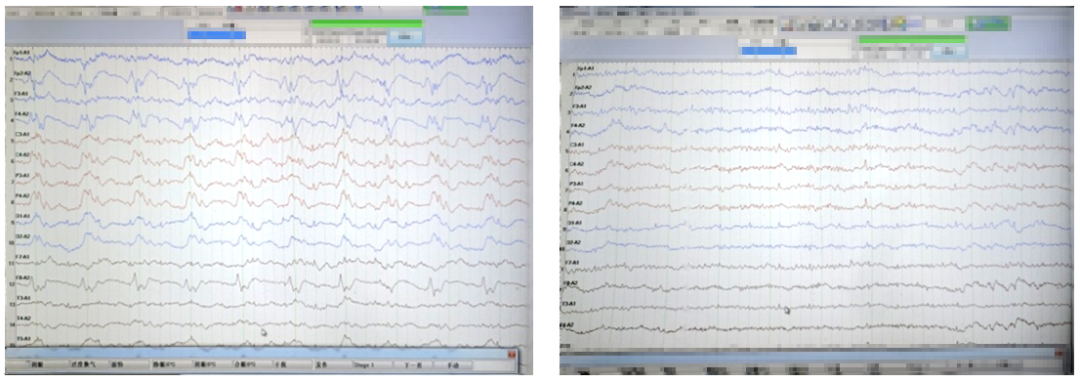

图上显示患者右侧额极、额、前颞区持续性周期样放电,如此真像大白,原来患者反应迟钝是发生了非惊厥性癫痫持续状态,癫痫并没有有效控制。于是在脑电监测下静推咪达唑仑,推注后,我们看到癫痫样放电消失,患者反应也恢复了正常。